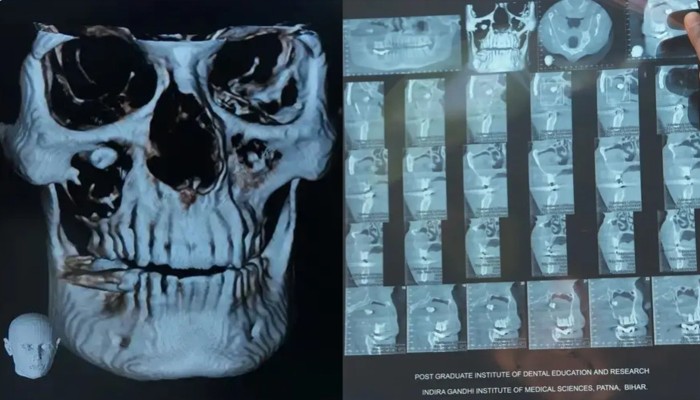

বিরল অস্ত্রোপচারে চোখ থেকে দাঁত অপসারণ ​চিকিৎসকরা জানিয়েছেন, এই জাতীয় সমস্যা খুবই বিরল এবং ওই দাঁত অপসারণের সার্জারি বেশ জটিল ছিল। ছবি : বিবিসি

‘আমার সব কাজ আটকে গিয়েছিল। এরপর জুন মাসে আমি আইজিআইএমএসে দাঁতের চিকিৎসকের কাছে যাই। চিকিৎসক আমার সিবিসিটি স্ক্যান করান। সেখান থেকে জানতে পারি আমার চোখে দাঁত গজিয়েছে।’

সিবিসিটি সিস্টেম এমন এক ধরনের ডায়াগনস্টিক ইমাজিং টুল, যেখানে এক্স-রে রশ্মি ব্যবহার করে হাড় ও সফট টিস্যু, বিশেষ করে মাথা ও মুখ বা ‘ওরাল’ এরিয়ার হাই রেজল্যুশনের থ্রিডি ইমেজ পেতে সাহায্য করে।

রোগী রমেশ কুমারের যখন ‘কোন বিম কম্পিউটেড টোমোগ্রাফি’ বা সিবিসিটি করানো হয়, তখন দেখা যায়, তার দাঁতের গোড়া ‘ফ্লোর অব দ্য অরবিটে’ রয়েছে। ডা. প্রিয়ঙ্কর সিং ব্যাখ্যা করেন, ‘এই ক্ষেত্রে, দাঁতের গোড়া ছিল ফ্লোর অব অরবিটে। যদিও এর ক্রাউন (দাঁতের সাদা অংশ) ছিল ম্যাক্সিলারি সাইনাসে। যেহেতু এই দাঁত নিজের স্বাভাবিক স্থানে গঠিত হয়নি, তাই শরীরের কাছে এটা ফরেন বডি ছিল।’